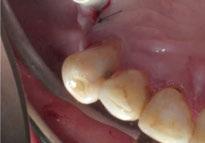

directamente a cabeza de implante para realizar una prótesis dentoalveolar de cerámica de 3 piezas, que equilibraran la oclusión y dieran soporte al labio y la mejilla (Figuras 14-17)

Figura 14. Imagen intraoral frontal postoperatoria al año de la reconstrucción.

Figura 15. Detalle de prótesis dentoalveolar cerámica en visión lateral.